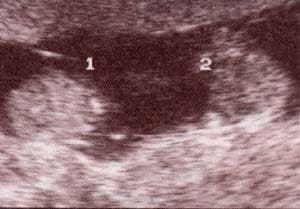

| fig. 54. – (a).gemelar monocorial – monoamniótico. 12 semanas. corte longitudinal. se observa única masa placentaria y ausencia de membrana divisoria. |

fig. 54. – (b).gemelar monocorial – monoamniótico. 12 semanas. corte longitudinal. se observa única masa placentaria y ausencia de membrana divisoria. |

fig. 55. embarazo múltiple. 5 semanas.se observan tres

sacos gestacionales bien definidos correspondiente a fecundación in vitro.